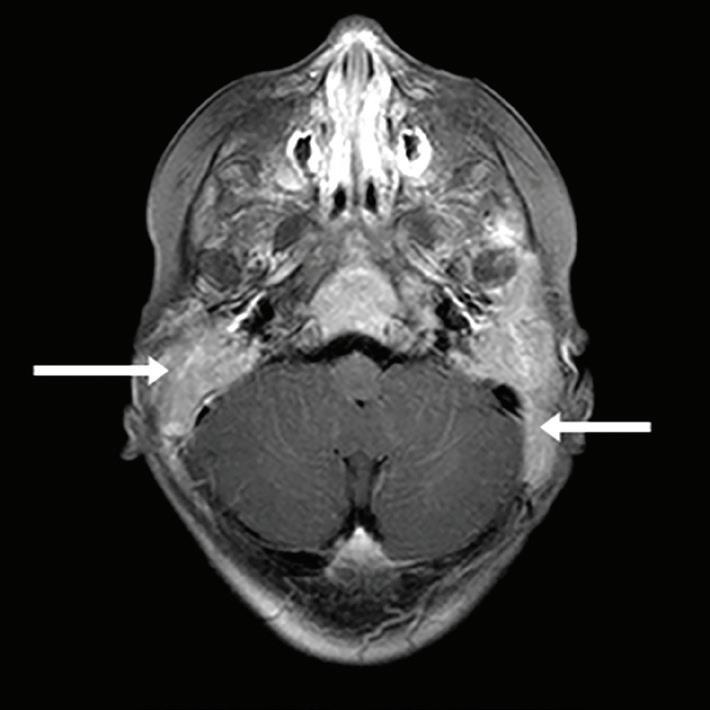

All CT scans were obtained from a 16-slice scanner CT machine (Siemens; Munich, Germany), with 0.6 mm between two slices, in the Amir-Alam University Hospital affiliated with Tehran University of Medical Sciences. The CT scans were not obtained for this study but rather for other indications. In the CT scan, the axial plane that showed the common crus of the posterior semicircular canal (figure) with better IAC visualization was selected.

KOUHI, ZARcH, POUyAN Figure. This CT scan of the axial plane shows the common crus of the posterior semicircular canal.

IAC exposure by drilling. P1 indicates the maximum proportion of IAC that can be exposed by drilling while preserving the posterior semicircular canal. Range of the mean P1 was 0.53 to 0.64 in the three groups, and the average was 0.61 ± 0.09 (table 3). This proportion of IAC was not significantly different between the three groups (p > 0.05). Maximum exposure (0.82) was observed in normal temporal bones (with no otitis or vestibular schwannoma). Pneumatization of the posterior or anterior petrous apex or the extent of mastoid pneumatization was not related to this exposure (p > 0.05). In patients with vestibular schwannoma or otitis, no significant difference was observed between the affected and normal side (p > 0.05).

Posterior semicircular canal drilling probability. In all groups of patients, the A1 angle was wider than the A2 angle, indicating that drilling from the porus to the fundus of the IAC is not achievable without removing the posterior semicircular canal (table 3). We also discovered that A1 was always wider than A2, except in one temporal bone. These angles were similar in temporal bones with different pathologies (p > 0.05).

Endoscope vision vector. The mean A4 angle was 103° (standard deviation: 11.96°; range: 76.5 to 128.7°). In 56% of temporal bones, this angle was <105°, which means that even with a 30° endoscope, the fundus cannot be visualized (assuming a 45° visual width and a 30° midline vision vector). However, in >91% of the cases, the fundus was observed using a 45° endoscope.